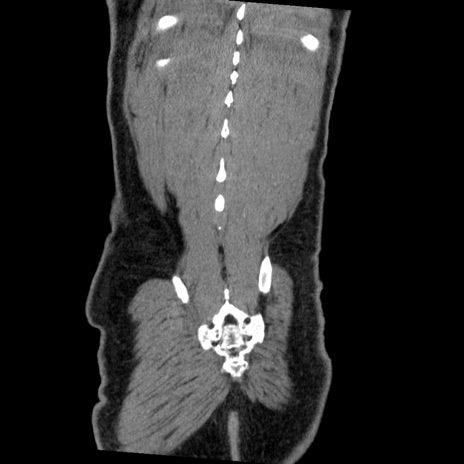

症例22(冠状断像)

【症例】50歳代男性

【主訴】腹痛

【現病歴】AVMからの被殻出血のため回復期リハ病棟入院中。 本日午後3時頃急に下腹部痛が出現した。

【既往歴】AVM、被殻出血、虫垂炎、高血圧

【身体所見】意識晴明、左半身不全麻痺、会話の理解は良好、36.5°C、腹部:膨隆、全体に板状硬、下腹部正中に圧痛点あり、反跳痛-、筋性防御不明、右下腹部にope scar

【データ】WBC 9400、CRP 0.06